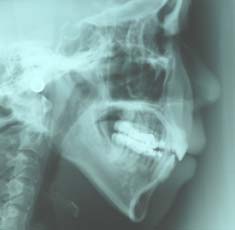

治療後

3.下顎前突(受け口) 下の歯が上の歯より出ています

治療前